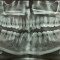

Alo dok, mau bertanya. Kalo misalnya kita (dr umum) dpt pasien yg dtg dengan keluhan mau cabut gigi tapi tensi nya itu tinggi. Apakah boleh saat itu juga diberi obat antihipertensi lalu observasi sebentar lalu dicabut giginya, atau harus datang kontrol ulang untuk lihat apakah dia mmg benar HT atau hanya sedang merasa takut (krn mau cabut gigi)? Terima kasih dok 🙏🏼

ALO Dokter, setuju dok, tekanan darah bisa meningkat akibat rasa sakit (dari giginya) atau ketakutan, dan ini bukan hipertensi. Sebaiknnya, tekanan darah pasien harus diperiksa ketika tidak kesakitan/stres dan saat istirahat, sedangkan terapi antihipertensi diberikan berdasarkan faktor risiko kardiovaskular.

Tidak ada bukti bahwa tekanan darah tinggi berhubungan dengan dampak buruk selama atau setelah prosedur perawatan gigi, jadi prosedur perawatan gigi tidak boleh ditunda jika tekanan darah tinggi.